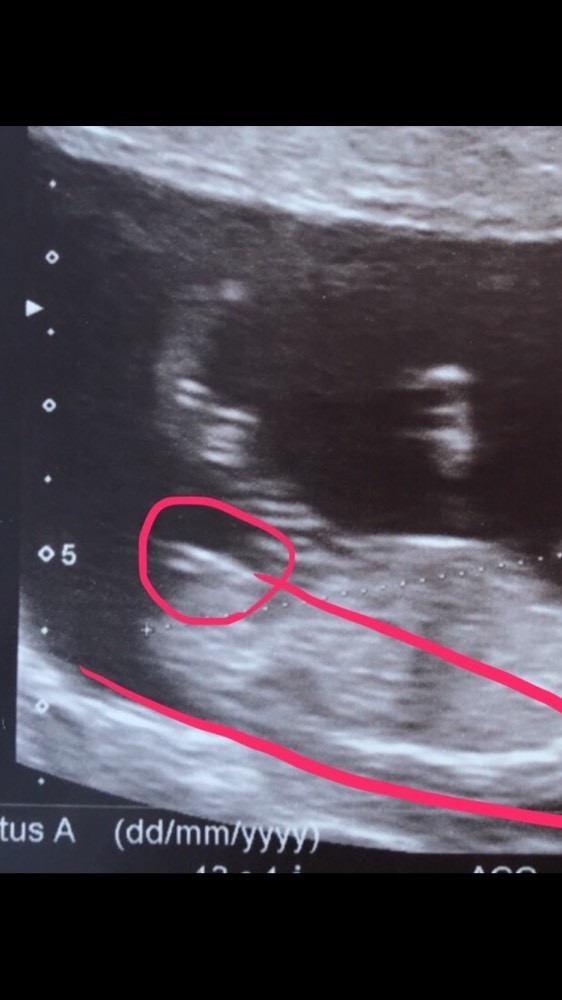

Peut on se tromper à l'échographie. Il peut y avoir le cordon entre les jambes le bébé peut avoir les cuisses serrées ou bien moins de liquide amniotique. Mais nempêche que suis un peu déçu parce que jattendais un garçon comme premier enfant. Peut-on se tromper à léchographie - aufemini.

En cas daplasie vaginale avec utérus fonctionnel. Léchographie ne peut pas se tromper par contre le médecin qui te passe ton échographie lui peut se tromper. Il y a en effet des questions de géométrie dangle et de positionnement du foetus à lintérieur du ventre de la mère à.

Pour ma 2nde. Pour une échographie vésicale il faut avoir la vessie pleine afin quelle apparaisse clairement sur lécran. On peut se tromper de sexe à la première échographie mais à la seconde ou la dernière cela relève de lexceptionnel.